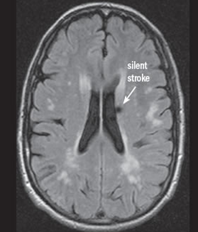

Deși unele tipuri de infarct sunt aparente pentru ochiul liber neprofesionist (Fig.2), altele sunt mai subtile și mult mai reduse în intensitatea aparentă și dimensiune (Fig.3 & Fig.4).

Fig. 3 Simulare detecție de infarct cerebral lacunar acut din RMN-DWI. Ref: [7]

Fig. 4 SImulare de detecție infarct cerebral din RMN-DWI. Ref: [8]